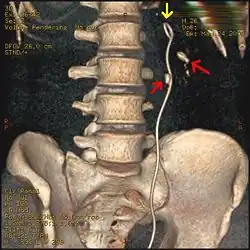

Otherwise a noncontrast helical CT scan with 5 millimeters (0.2 in) sections is the diagnostic method to use to detect kidney stones and confirm the diagnosis of kidney stone disease.[16][57][61][66][7] Near all stones are detectable on CT scans with the exception of those composed of certain drug residues in the urine,[59] such as from indinavir.

Measurement of a 5.6 mm large kidney stone in soft tissue versus skeletal CT window.